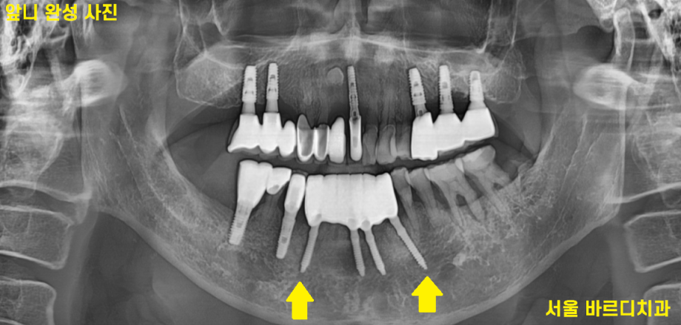

230627

정확한 검사를 시행해 보니

더욱더 확실해졌습니다.

까맣게 된 것이 다 뼈가 녹은 부위입니다.

치아가 손으로 밀어도 흔들린다는 것은

잡고 있는 뼈가 거의 없다는 것

역시나 사진에서 잇몸뼈가 녹아내린 것이 확인

그냥 손으로 잡아 뽑아도 뽑힐 정도였습니다.

발치 후 바로 강동구 치과에서

앞니 임플란트 수술을 진행하였습니다.

어금니는 이를 뽑고 기다리기도 하지만

앞니는 뼈가 얇아

주로 발치와 동시에 수술을 진행합니다.

6개의 앞니가 없었지만

4개의 임플란트 식립하고

머리는 6개로 만들어드리는 것으로

계획을 잡아 진행하였습니다.

231027

수술 후 3개월 뒤

충분히 임플란트와 내 뼈가 붙고 난 것을 확인

임플란트 머리를 만드는 작업을 했습니다.

231120

강동구 치과 앞니 임플란트 완성 사진입니다.